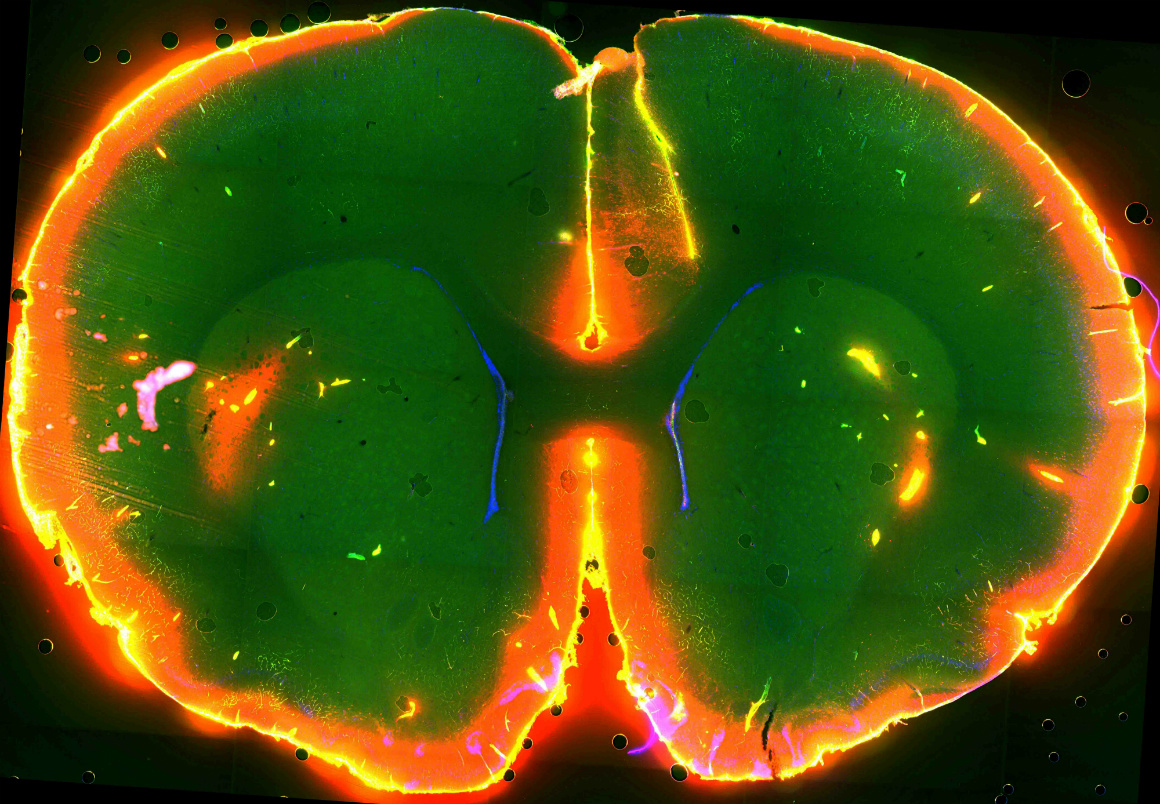

Os cientistas conseguiram ver fluir um líquido pigmentado no cérebro de ratinhos CORTESIA DO LABORATÓRIO DE MAIKEN NEDERGAARD

O novo estudo revela que o chamado sistema “glinfático”, identificado pela mesma equipa no ano passado no ratinho – e que o cérebro utiliza para remover toxinas e outros subprodutos da actividade neuronal –, apresenta o seu maior nível de activação durante o sono.

Um outro resultado surpreendente obtido pela equipa (sempre no ratinho) foi que as células cerebrais “encolhem” 60% durante o sono. Esta contracção faz aumentar o espaço entre elas e permite que o líquido cérebro-espinal flua melhor, evacuando mais eficazmente os detritos pelo sistema glinfático - um autêntico sistema de "esgotos" do cérebro. Os cientistas especulam que a hormona noradrenalina (menos activa durante o sono) poderá ser o “interruptor” que controla a contracção e expansão das células.